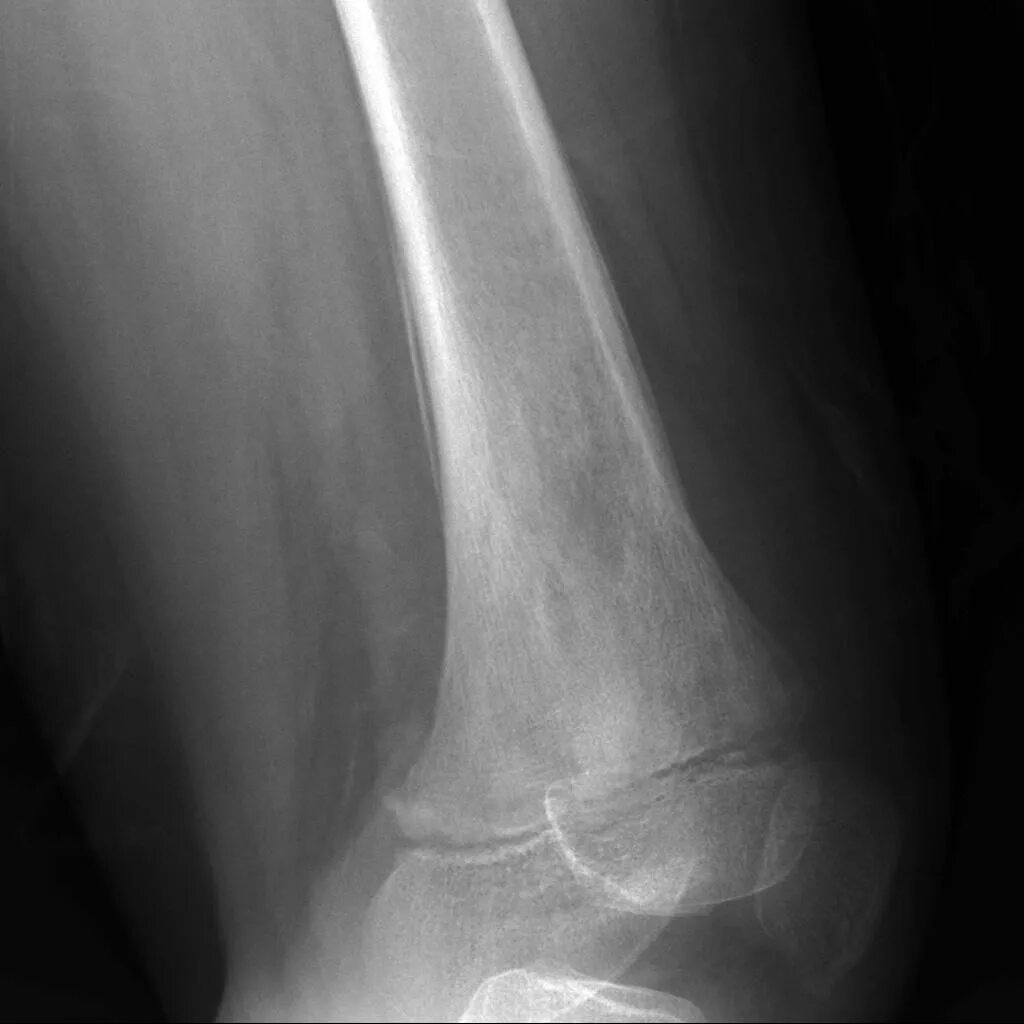

Sarcoma horror